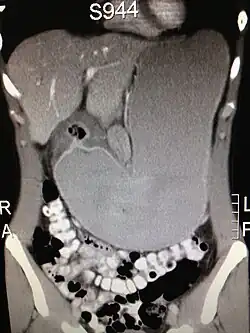

Die ergiebigste Untersuchungsmethode des Magens ist die Gastroskopie (Magenspiegelung). Bei der Magenspiegelung wird oft ein HU-Test zum Nachweis einer Helicobacter-Besiedlung entnommen. Außerdem sind gezielte Biopsien zur histologischen Untersuchung leicht möglich. Die Röntgenuntersuchung des Magens, die vor dem Aufkommen der Gastroskopie betrieben wurde, wird heute nicht mehr routinemäßig durchgeführt, da sie sehr unsichere Ergebnisse produziert. Die Ultraschalluntersuchung des Magens ist leicht möglich, liefert aber nur selten brauchbare Ergebnisse, wie zum Beispiel eine Magenausgangsstenose oder eine auffällige irreguläre Wandverdickung. Beim Ultraschall ist der Magenausgang recht gut, andere Teile wie z. B. die Cardia kaum beurteilbar. Eine Computertomographie des Magens ist ebenfalls nur in Ausnahmefällen sinnvoll. Zur Bestimmung von Helicobacter-Bakterien wird zunehmend ein Atemgastest durchgeführt.

Als Risikofaktoren des Magenkarzinoms, einer der häufigsten Krebsarten beim Menschen, sind bestimmte Ernährungsgewohnheiten, chronische Gastritis, Zigarettenrauch und Alkoholkonsum identifiziert. Das Risiko, an Magenkrebs zu erkranken, ist bei erblicher Belastung erhöht (was vermutlich mit der erblichen Übertragung des Bakteriums Helicobacter pylori zusammenhängt) – es besteht ein 3,7fach erhöhtes Risiko für Verwandte ersten Grades. Menschen mit der Blutgruppe A sind häufiger betroffen. Die Ursache ist unbekannt. Die Therapie des Magenkarzinoms erfolgt zurzeit hauptsächlich operativ,[1] etwa mittels Gastrektomie.